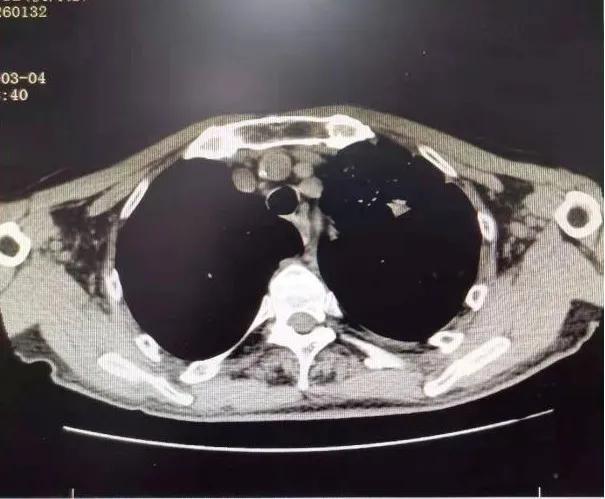

1个月后张爷爷来院复诊,复查胸部CT提示:左肺上叶肿块缩小到1cm,肺不张明显缓解,胸腔积液减少 。 张爷爷表示近1月来状态明显好转,未再咯血,活动也不像之前那样一动就喘,平时走路吃饭都不影响。入院后PS评分1分,临床疗效评估为PR。 为更好的控制肿瘤,进行了第二次介入治疗。 行支气管动脉及胸廓内动脉造影后显示肿瘤染色明显减少,继续灌注化疗药物后,将肿瘤滋养动脉进行了彻底栓塞。 术后无不适, 顺利完成第二次治疗。

第二次介入造影显示肿瘤供血动脉减少及肿瘤染色明显减轻